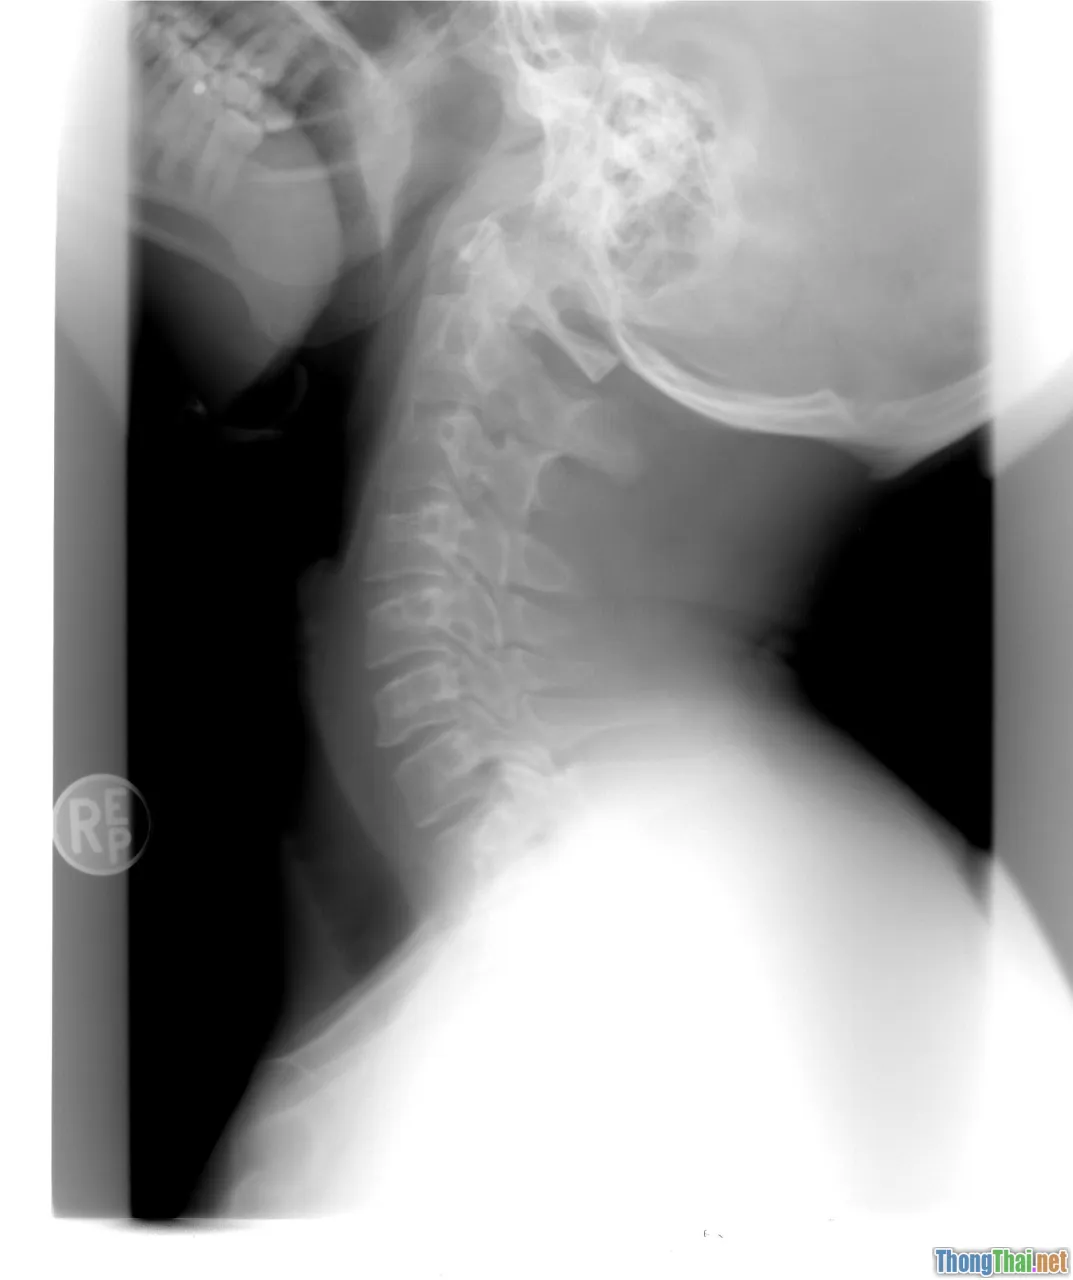

Sơ Cứu Chấn Thương Cột Sống, Đầu, Cổ: Tuyệt Đối Không Di Chuyển Tùy Tiện

spine injury, neck brace, immobilization

Đặc biệt nghỉ nhớ: Gần 30% di chứng liệt tứ chi do tay cứu hộ di chuyển sai cách! Với nạn nhân nghi ngờ chấn thương sọ não, cột sống (tai nạn giao thông, ngã cao, bất tỉnh sau va đập mạnh):

• Tuyệt đối không nâng dậy bừa bãi.

• Không kéo xốc nạn nhân bằng cánh tay, vai, chân hoặc kéo lê.

• Nếu bắt buộc sơ tán khỏi chỗ cháy, khẩn nguy, hãy giữ nguyên cổ, đầu-vai-lưng trên 1 đường thẳng (có thể dùng áo/khoác hoặc vài người phối hợp di chuyển đồng bộ).

Tác động của việc sơ cứu đúng

• Ngăn biến dạng tuỷ sống khiến từ nạn nhân khả năng hồi phục thành người mất vận động trọn đời;

• Tránh sốc, suy hô hấp thứ phát do tổn thương não hoặc hô hấp tắc nghẽn;

• Mọi việc di chuyển – xoay đầu – bẻ cổ chỉ làm khi thực sự cần giải nguy hiện trường mạng sống toàn bộ.

Bên cạnh đó, luôn đề nghị người chứng kiến gọi 115 hoặc lực lượng cấp cứu chuyên nghiệp sớm nhất.